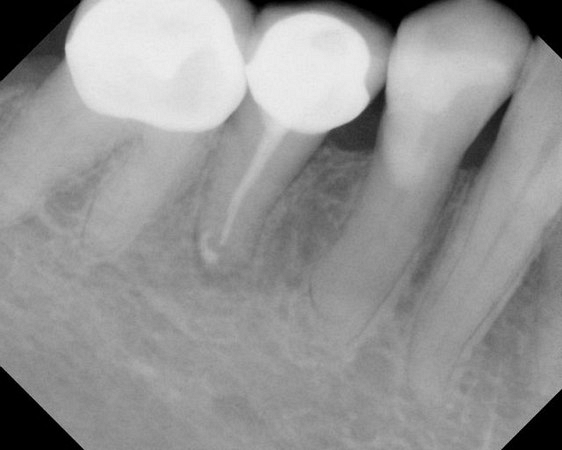

Here are examples of digital dental radiography